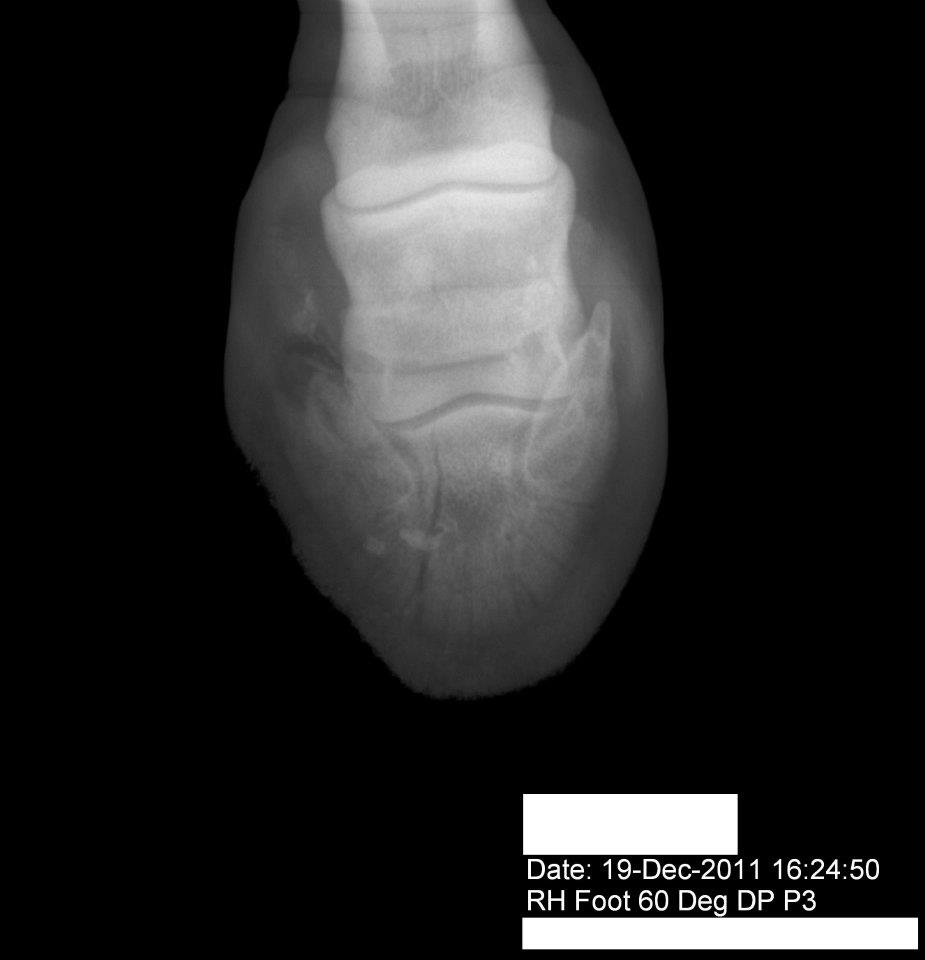

Piper's Fractured Coffin Bone | HorseDVM

Piper's Fractured Coffin Bone | HorseDVM from www.horsedvm.com

There are many different types of fracture from greenstick, hairline, and compression to oblique, impacted, and longitudinal. A fracture, simply put, is a broken bone. A fracture caused by a. Affected foals would be lame and would require stall rest for 30 to 60 days. What are the signs of a coffin bone fracture? Coffin bone fractures are often difficult to diagnose. Some are more severe than others, depending on the. Broken bones are very common in childhood, although. Coffin bone fractures can occur in seven different types! Coffin bone fractures in foals were one of the common problems we were experiencing. Pay attention to their weight bearing when your hand walking so you can tell the vet what you're seeing before they arrive. The most common broken bones are stress fractures, rib fractures, skull fractures, hip fractures, and fractures in children. These coffin bone fractures, however, appear to be closely linked to sound horse fracture shoes are sized to fit foals in the age group that appears to be most likely to have coffin bone. Since there is no obvious signs of a fracture (swelling or pain on palpation), and lameness varies depending on the portion of the bone that's. Distal phalangeal fractures can be classified into one of seven types.2,6,7 type i is a non articular fracture of the palmar process (wing) of the distal phalanx. Bone fractures, orthopedic, the bone & joint center. The coffin bone, also known as the pedal bone (u.s.), is the bottommost bone in the front and rear legs of horses, cattle, pigs and other ruminants.